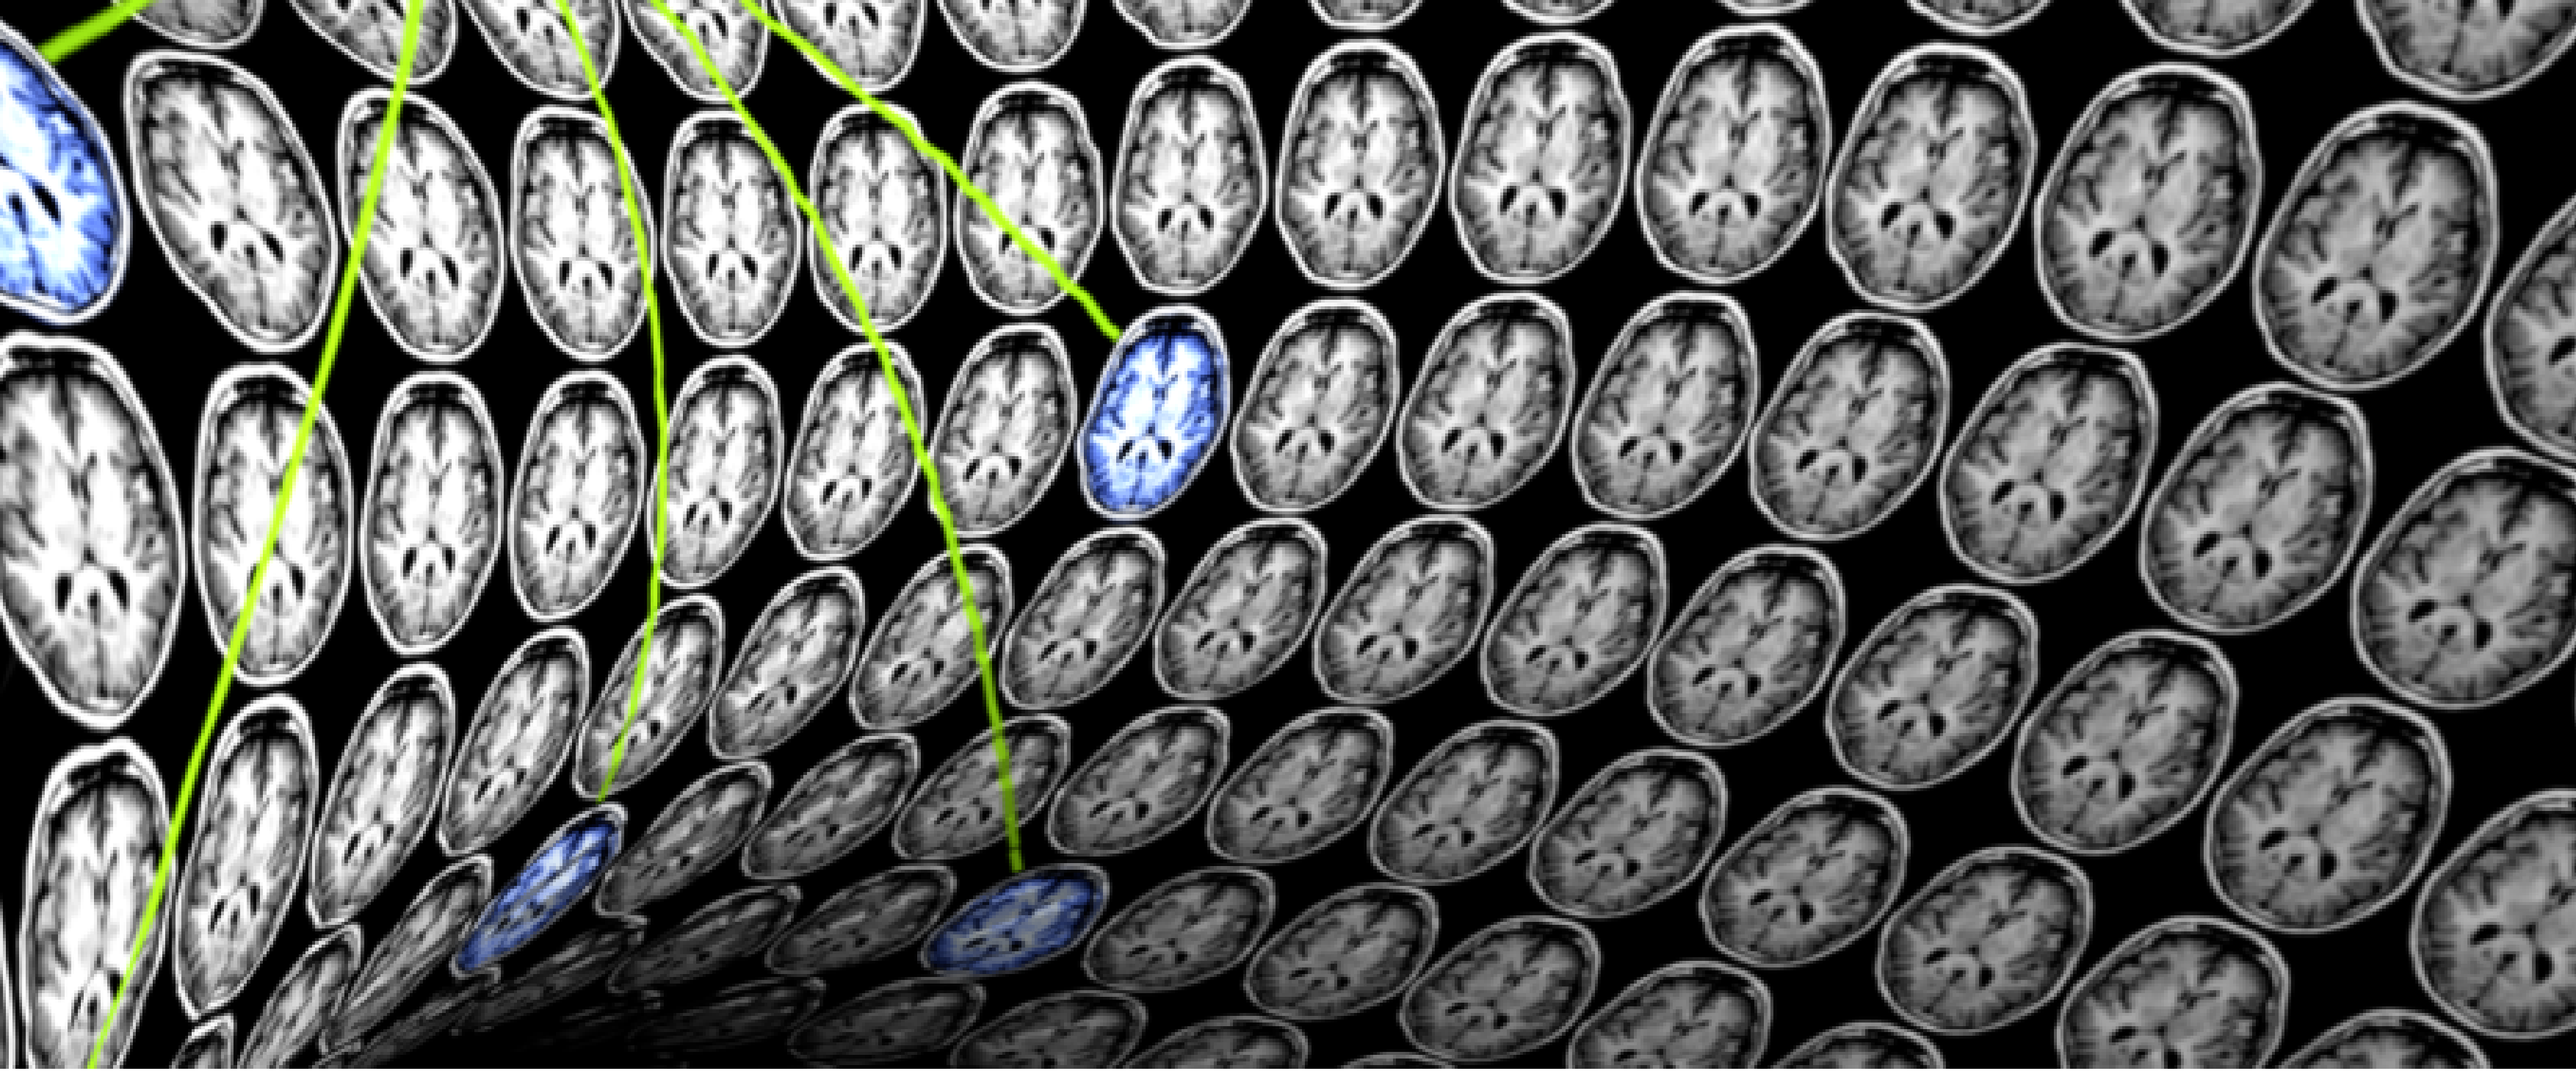

La Semaine du Cerveau 2020 à Neurospin

Du 16 au 20 mars 2020 @ Neurospin - 91190 Gif-sur-Yvette

La Semaine du Cerveau a pour but de sensibiliser le grand public à l'importance des recherches dans le domaine des neurosciences. Parmi les experts intervenants, Bertrand Thirion, directeur de l'équipe Parietal Inria / CEA et directeur de l'Institut DATAIA.

3e colloque sur l’imagerie médicale à l’heure de l’intelligence artificielle

22 avril 2020 @ Institut du Cerveau (ICM) - 75013 Paris

Ce colloque, soutenu par l'Institut DATAIA, est dédié aux algorithmes en médecine. Ses deux centres d’intérêt principaux sont l’analyse automatique des images médicales et la collecte et l’analyse de grandes données, désormais permises par l’informatisation du suivi des patients.